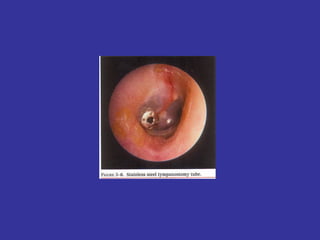

Timpanostomy Tubes:   Insertion of ventilation tubes in the TM for ventilation/drainage. (Silicone) most recent development  Incision on Anterior Inferior region. Not responding to ATB treatment Recurrent AOM infections in a period of time *Uni or bilateral chronic OME  for more than 3 months. *Conductive hearing loss in excess of 30 dB in patients with  Otitis media with Effusion  *Recurrent AOM infections: Children with > 3 separate episodes within 3 months Children with  4 episodes in a 6 months period or  with  6 episodes in a 12 months period